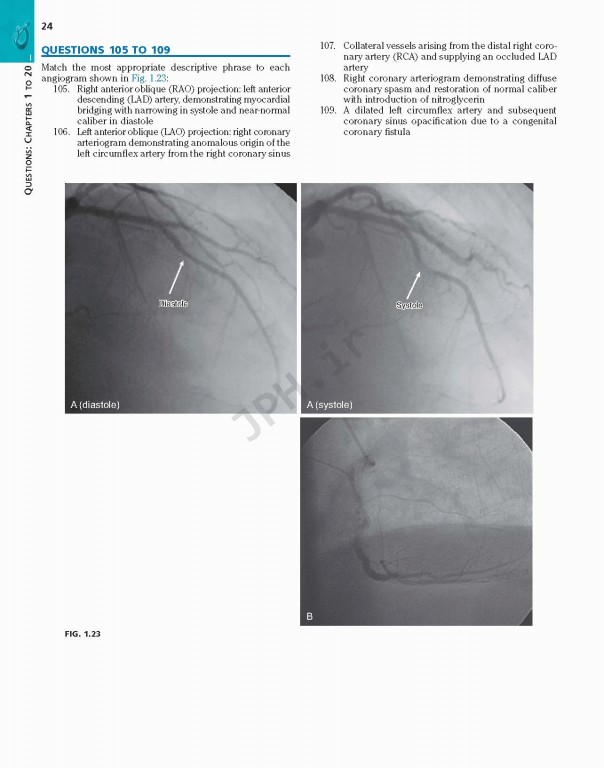

کتاب Braunwalds Heart Disease Review and Assessment 2019، بررسی و ارزیابی بیماری قلبی براونوالد ویراست یازدهم شامل تصاویر و تصاویر کاملاً رنگی که مطالعه شما را بهبود بخشیده و حفظ مواد پیچیده را بهبود می‌بخشد.

With more than 700 review questions derived from and keyed to the newly revised 11th Edition of Braunwald's Heart DiseaseBraunwald’s Heart Disease Review and Assessment, 11th Edition, is the perfect review tool for fellows, residents, and practitioners to prepare for board exams in cardiovascular medicine. Noted Harvard educator Dr. Leonard S. Lilly, with assistance from faculty and fellows at Brigham & Women’s Hospital, provides a thorough, clear, and concise overview of the entire field, helping ensure your mastery of all key aspects of today’s cardiology. This title is a one-stop resource for complete, authoritative coverage of the most important concepts in cardiovascular medicine – ideal for self-assessment, individualized study, and clinical practice.

• Contains full-color images and illustrations throughout, and numerous case studies that enhance your study and improve retention of complex material.